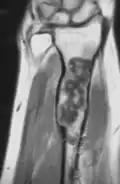

Magnetic resonance imaging (MRI), ultrasound, and scintigraphy are generally not practical for diagnostic purposes. X-rays are not as effective in the monitoring or evaluation of enchondromas due to frequent localized changes also sometimes due to the large number of enchondromas. MRI can sometimes however be used to monitor and evaluate symptomatic lesions in the case of potential malignant transformations.